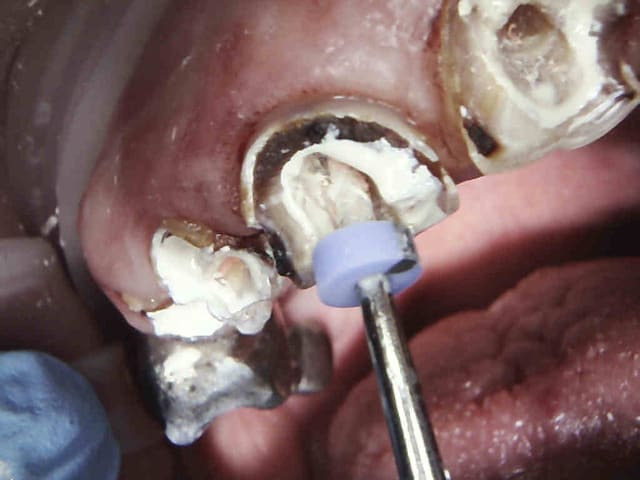

Gutta scellée au tubuli seal avec ou sans condensation thermo mécanique.

Logement du tenon réalisé au friendo ( voir photos) qui fond la gutta ( 200 ° au niveau de l'insert) . Un coup de machtou et hop tu peux passer les forets.

Avantage tu peux faire les provisoires et l'empreinte dans la séance et surtout tu peux raser les couronnes ce qui est un réel plus pour les endos surtout avec des pulpes rétractées comme ici ca évite de faire des conneries avec un abord palatin ou on ne voit rien du tout.

A 200 ° le plugger heater le ciment de scellement de cone tubuli seal prend fissa. Et pas de spray. ( logement fait avant l'obturation au largo puis la gutta thermocompactée de la longueur du tenon est virée au plugger heater , reste à passer un foret pivomatic). En un temps ca permet de raser les antérieures avant de faire l'endo, ca dégage le champ de vision et on centre mieux pour atteindre la pulpe meme rétractée.